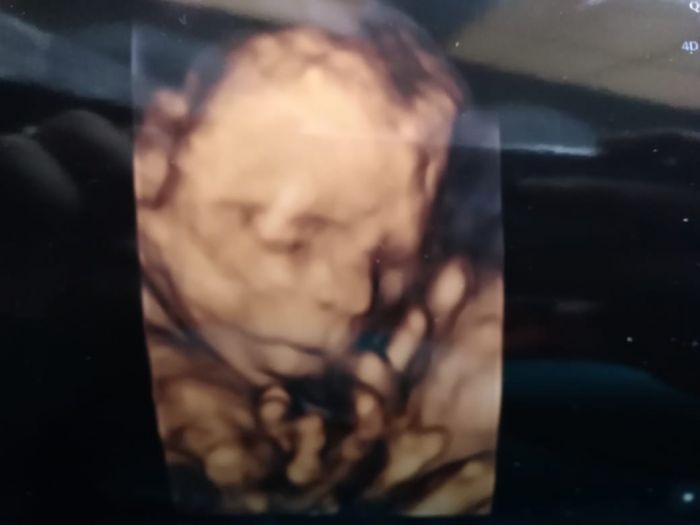

včerejší screening dopadl na 1.Všechno je v porádku.Jen jsem zvědava co to budeme mit za dítě pořád ci cucal ruce,nohy nebo si sahal na šulinka.Přidávám foto.

[1073153] Blanko gratuluji, malej je nadhernej. Ja du 4 a uz ted jsem nervozni. Mimi ale kope jak fotbalista tak je snad vsechno ok.

Blanko moc gratuluji. Parádní fotka.